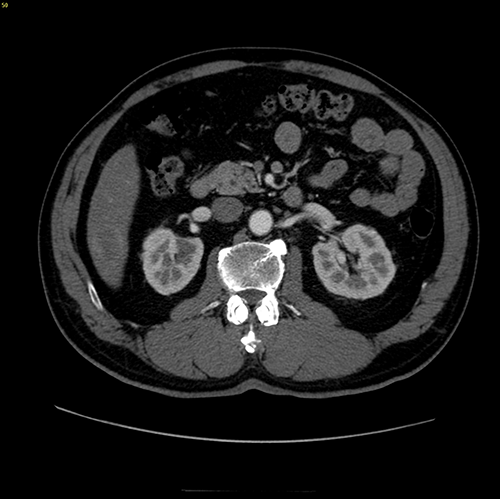

S6肝癌-腹腔镜S6切除